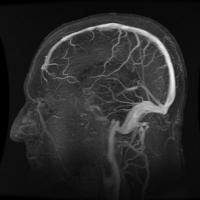

Brain Can Map Negative Spaces in the Body, Scientists Say

Sharon Moore December 20, 2012

There is no doubt that the human brain is very powerful. In a recent study by the University of South Australia, scientists discovered that the brain has the ability to know which part of the body is healthy or neglected. The brain knows what area hurts Their findings were part of a research about the spatial perception of people with complex regional pa